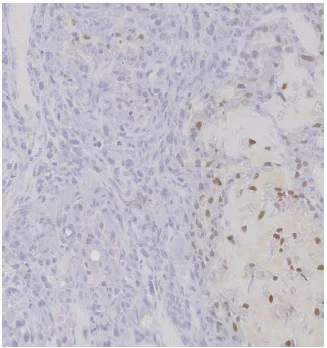

Immunohistochemical analysis of paraffin embedded mouse osteosarcoma tissue labeling Sp7/Osterix with ab22552 at 1/1000 (overnight at 4°C). Fixed 48h in 4% formol. Decalcified in 4% EDTA and 0.2% PFA pH7.4 before inclusion in paraffin. Biotin conjugated secondary 1h RT. Amplification StreptABC, substrate DAB.

This image is courtesy of Jérôme AMIAUD, Laboratoire de Physiopathologie de la Résorption Osseuse et Thérapie des Tumeurs Osseuses Primitives. We thank them for their important contribution to the validation of ab22552.